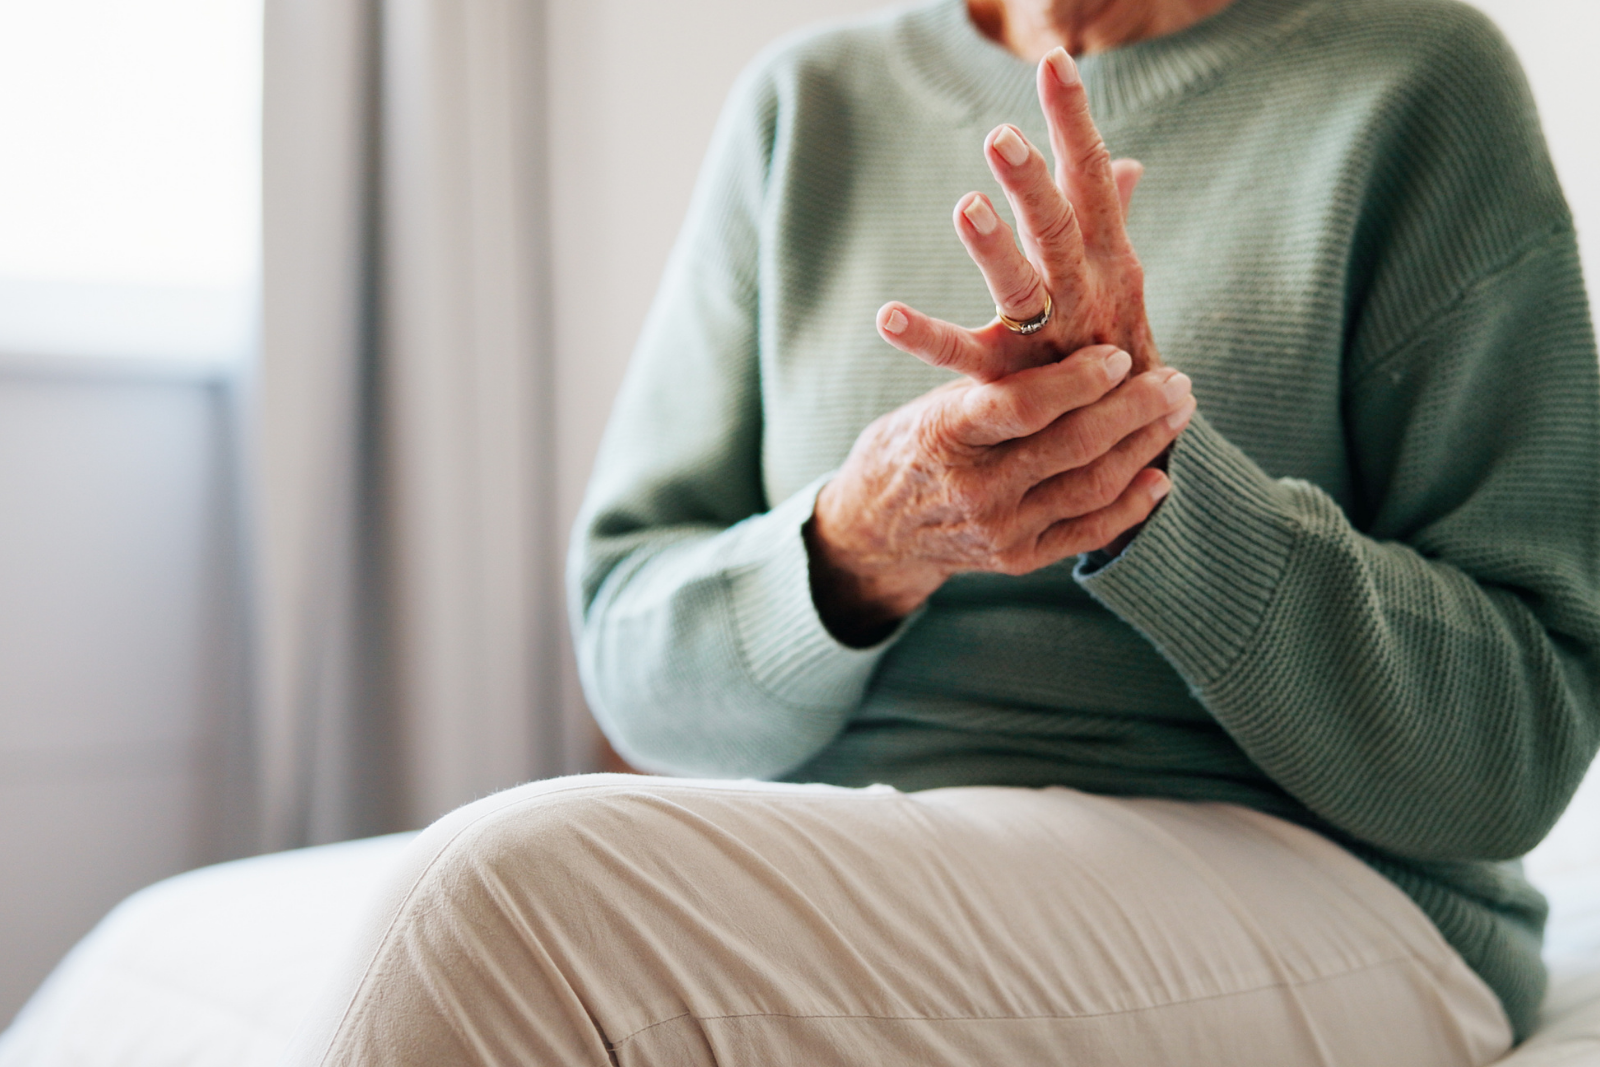

A dor crônica é caracterizada pela persistência da dor por mais de três meses e pode afetar diferentes regiões do corpo, como joelhos, ombros, cotovelos, punhos, pés, coluna e articulações em geral.

Dor crônica é a dor que persiste por mais de 3 meses, podendo manter-se mesmo após a cicatrização inicial do tecido. Ela pode envolver alterações musculoesqueléticas, articulares e do sistema nervoso, impactando sono, humor, mobilidade e qualidade de vida.

A Revitá atende pacientes com dor crônica em diferentes regiões do corpo, incluindo: